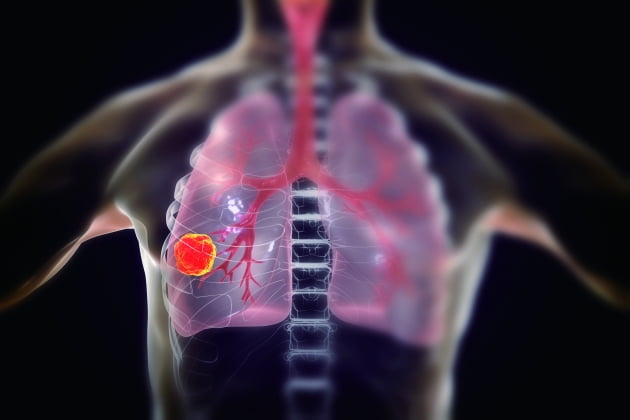

폐암은 다른 암에 비해 초기 단계에서 발견하기가 어렵기 때문에 정기 검진과 건강 관리를 통해 질병이 발병하지 않도록 예방하는 것이 중요합니다. 진단을 받았더라도 다양한 치료 방법이 있고, 최근에는 생존율이 높아지고 있기 때문에 전문가와 상의하여 포기하지 않고 치료를 지속하는 것이 중요합니다. 이번 글에서는 폐암에 좋은 음식과 폐암에 좋은 차에 대해 알아보았습니다. 내용 참고하시어 건강 관리하시기 바랍니다.